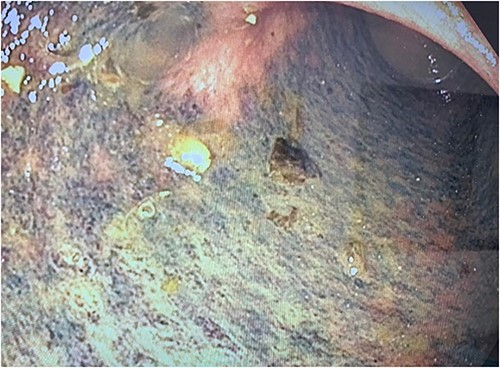

The colon was visibly dilated and macroscopically appeared viable with no external evidence of ischemia; however, on-table flexible sigmoidoscopy revealed an acute angulation at the rectosigmoid junction with evidence of mucosal ischemia distally (Fig. 3). Immediately adjacent to this area of obstruction extraluminally was the transplanted ureter with stent in situ. On discussion with her transplant surgeon, a de-functioning loop colostomy was created.

Photograph of the mucosal ischaemic changes in the part of the colon distal to the area of compression by the cord-like structure (presumably the stented ureter).